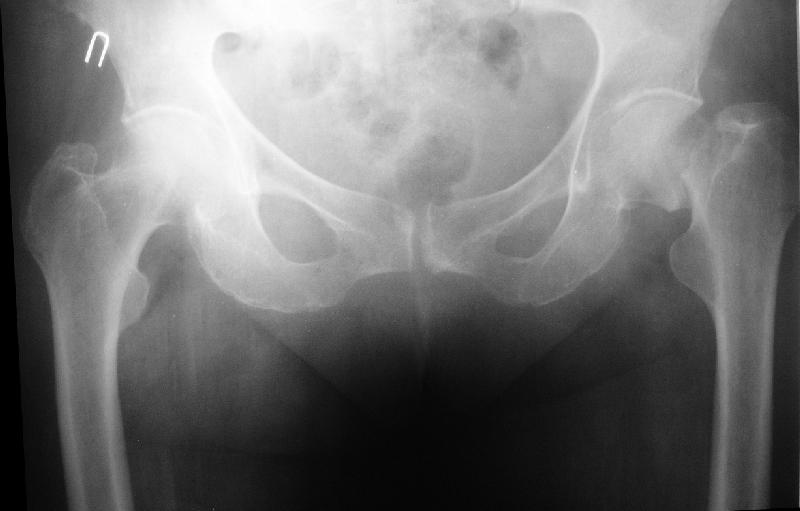

[Ortho] Перелом бедра, через неделю после эндопротезирования.

На прошлой неделе пациентке 74 лет, было выполнено цементное эндопротезирование тазобедренного сустава по поводу перелома шейки бедра.Активизирована на следующий день, ходила с костылями, нагрузка полная.Дело близилось к выписке, когда она, подскользнувшись упала в палате и получила то, что  видите на снимках.Что бы Вы стали делать в подобной ситуации? Заранее спасибо.